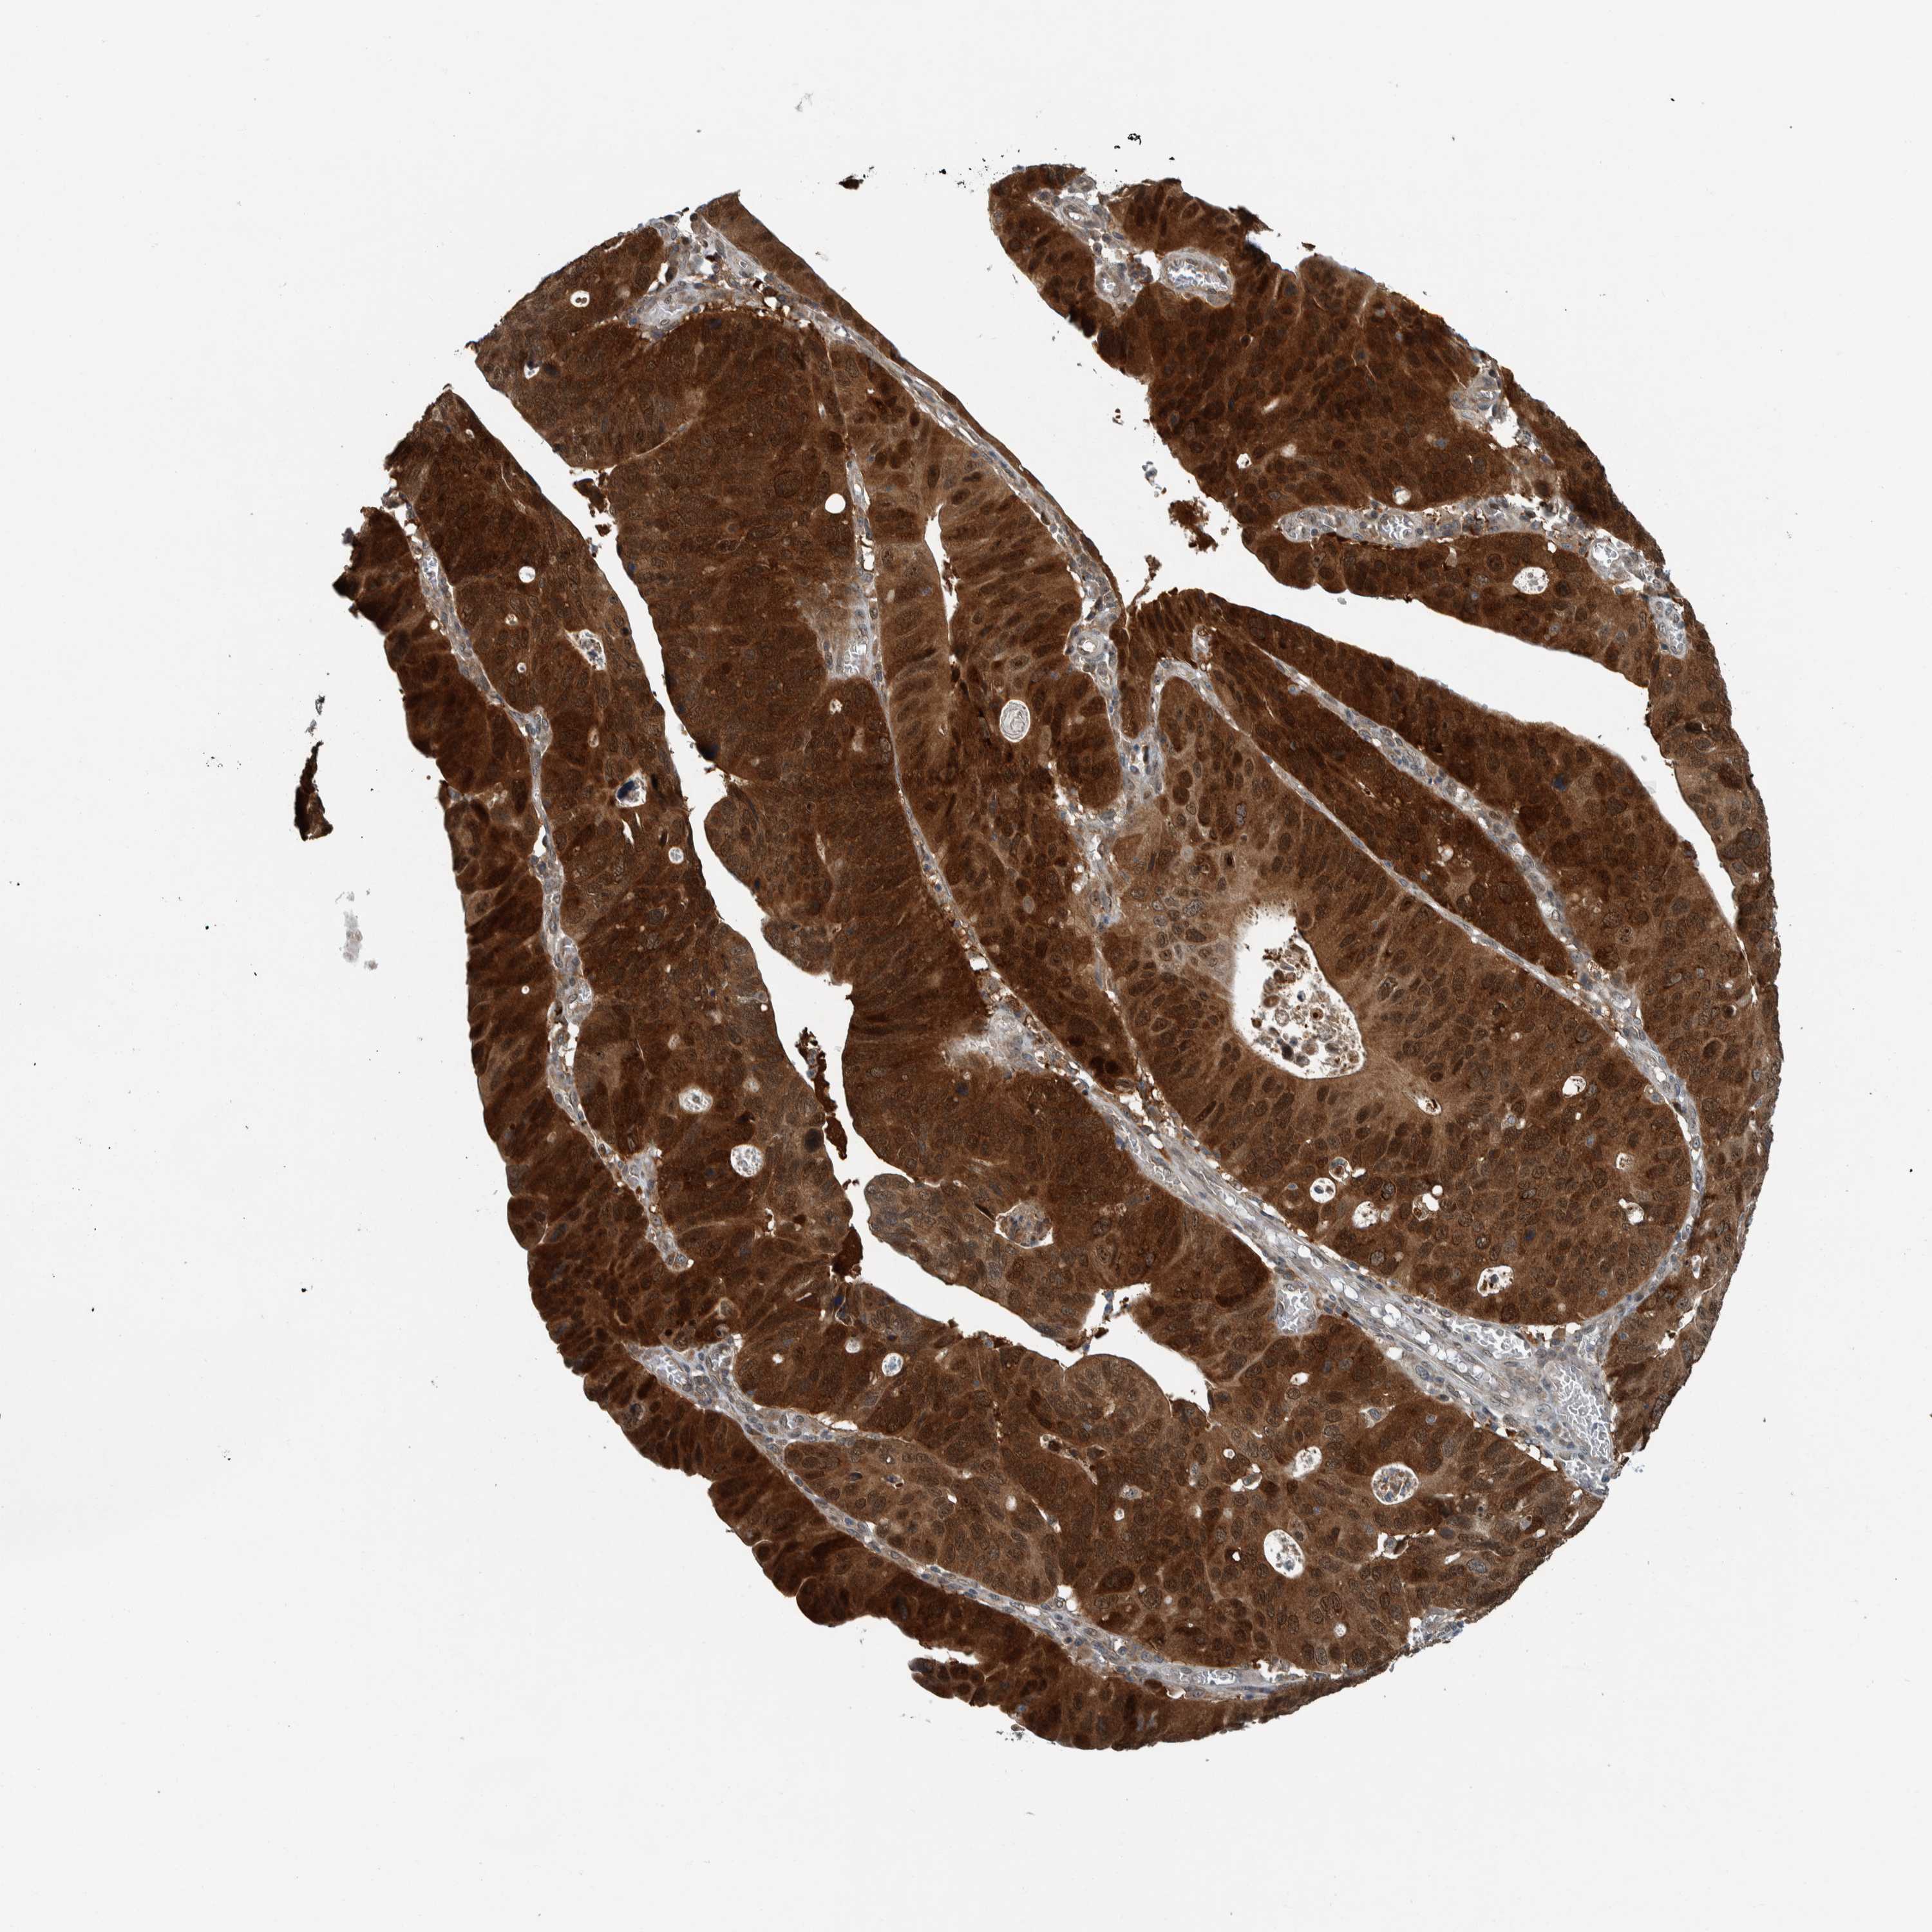

STOMACH CANCER - Protein expressioni

A mouse-over function shows sample information and annotation data. Click on an image to view it in a full screen mode. Samples can be filtered based on level of antibody staining by selecting one or several of the following categories: high, medium, low and not detected. The assay and annotation is described here.

Note that samples used for immunohistochemistry by the Human Protein Atlas do not correspond to samples in the TCGA dataset.

Antibody stainingi

Antibody staining in the annotated cell types in the current human tissue is reported as not detected, low, medium, or high, based on conventional immunohistochemistry profiling in selected tissues. This score is based on the combination of the staining intensity and fraction of stained cells.

Each image is clickable and will lead to virtual microscopy that enables deeper exploration of all samples and also displays staining intensity scores, fraction scores and subcellular localization as well as patient and tissue information for each sample.

Antibody HPA018402

Antibody HPA023959

Staining

High

Medium

Low

Not detected

Intensity

Strong

Moderate

Weak

Negative

Quantity

>75%

75%-25%

<25%

None

Location

Nuclear

Cytoplasmic/membranous

Cytoplasmic/membranous,nuclear

Adenocarcinoma, NOS